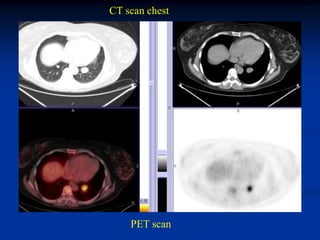

Case #1182.1 Metastatic leiomyosarcoma from uterus to hip

CT scans pelvis

PET scan

CT scan chest

Case #1182.1 Metastaticleiomyosarcoma from uterus to hip Axial T-2 57 yr female with hip pain 3 months Cor PD